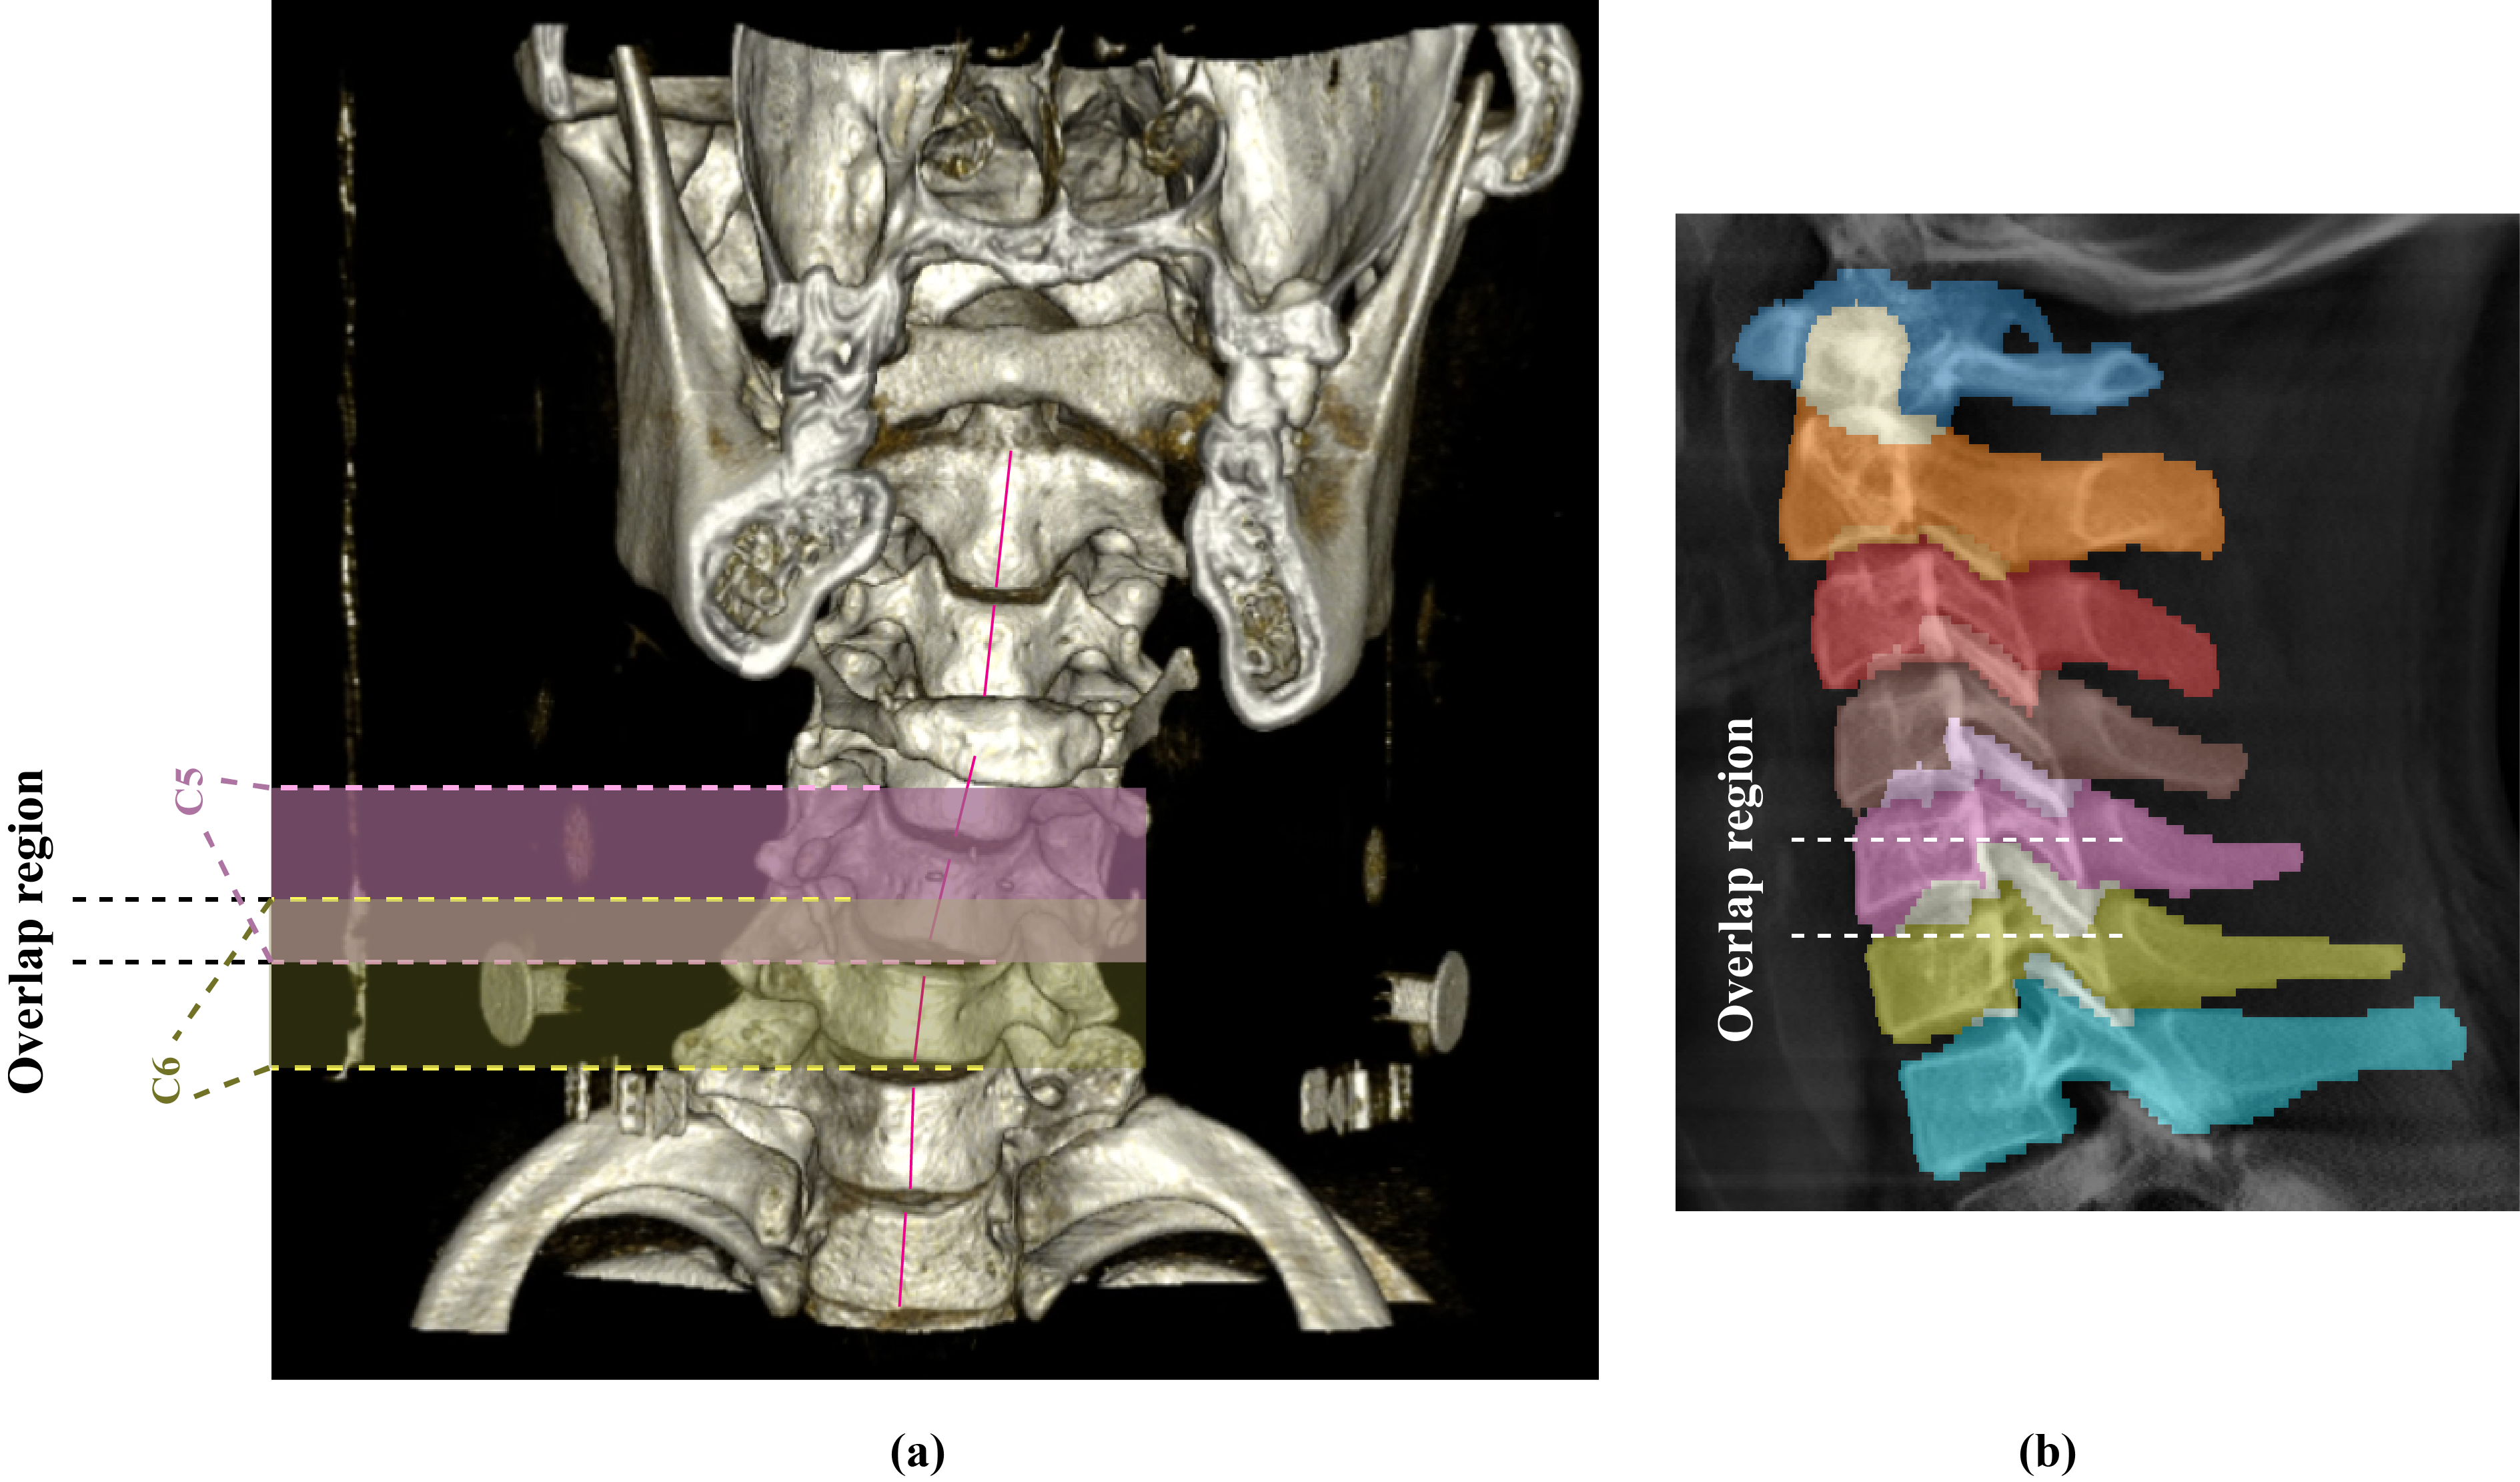

3.4.1 Multi-label Mask Generation

Since vertebra segmentation in this study is performed from coronal and sagittal projection images of the cervical spine VOI, anatomical overlap between neighboring vertebrae is frequently observed in these orthogonal views. Due to cervical curvature and non-linear neck alignment in most patients, distinct vertebral structures may project onto the same spatial location in 2D, causing a single pixel in the projection image to correspond to multiple vertebrae. Further details have been provided in Supplementary Section S4.1.

3.4.6 3D Vertebra Mask Estimation and Volume Extraction

Segmentation masks were predicted for coronal and sagittal projections of 2,019 patients. To maintain anatomical fidelity, outputs were reverse-resized and unpadded to original dimensions. We approximated 3D vertebra structure by extruding and intersecting the orthogonal masks. These 3D approximations were used to crop individual vertebrae volumes from all patient volumes. In total, 14,129 vertebrae were extracted; only ~4 were excluded due to noise-induced segmentation failure.